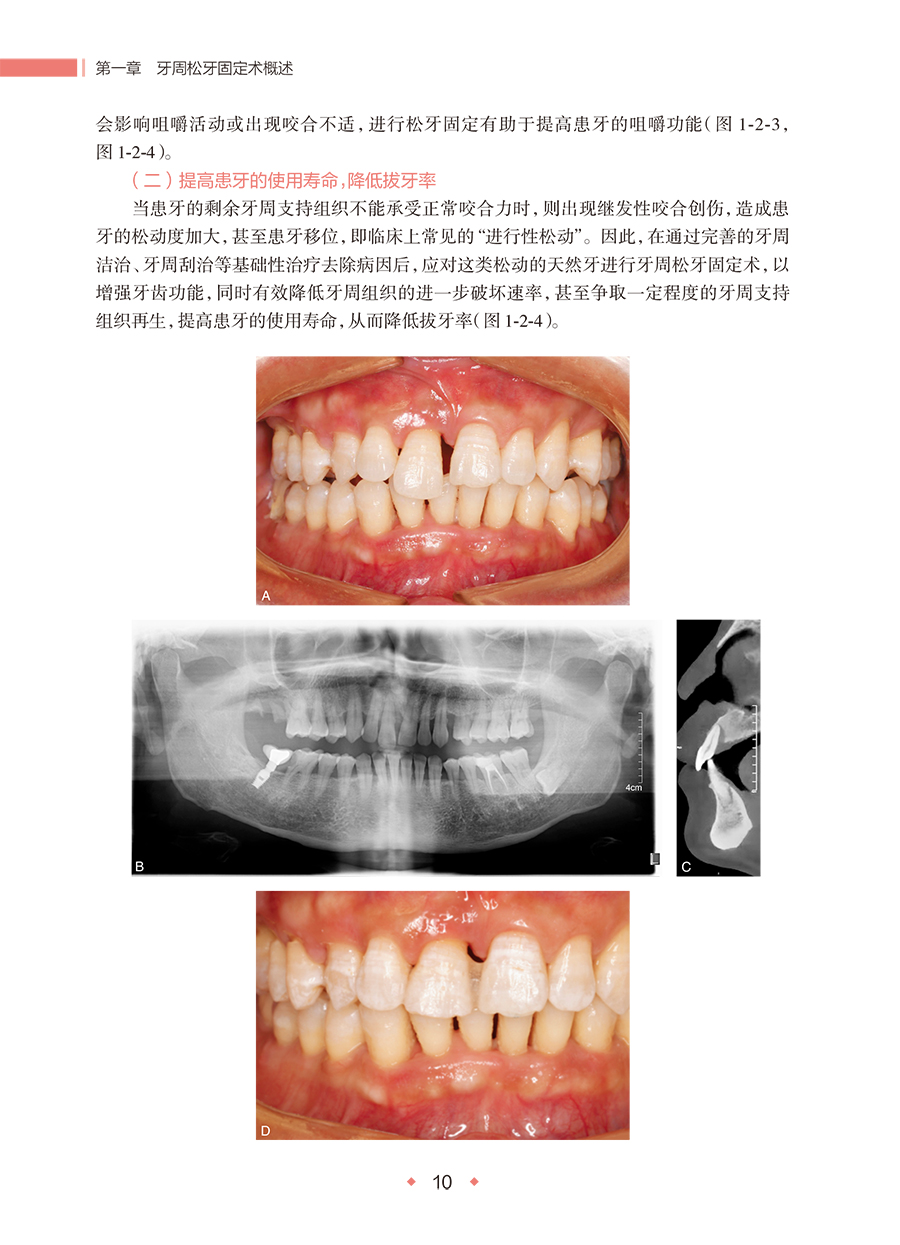

主要内容:本书详细介绍了牙周松牙固定术的操作流程和注意事项,包括患者的评估、器械的选择、操作步骤的规范操作、维护和康复指导等。结合大量的临床案例,帮助读者更好地理解和掌握牙周松牙固定术的应用技巧。此外,强调个性化治疗的重要性,针对不同患者的具体情况,提供了个性化的治疗方案和建议。 读者对象:口腔全科医生、牙周专科医生、口腔医学研究生及本科生等。兼顾理论性和实用性,对初学者和有一定经验的医生均有指导意义。